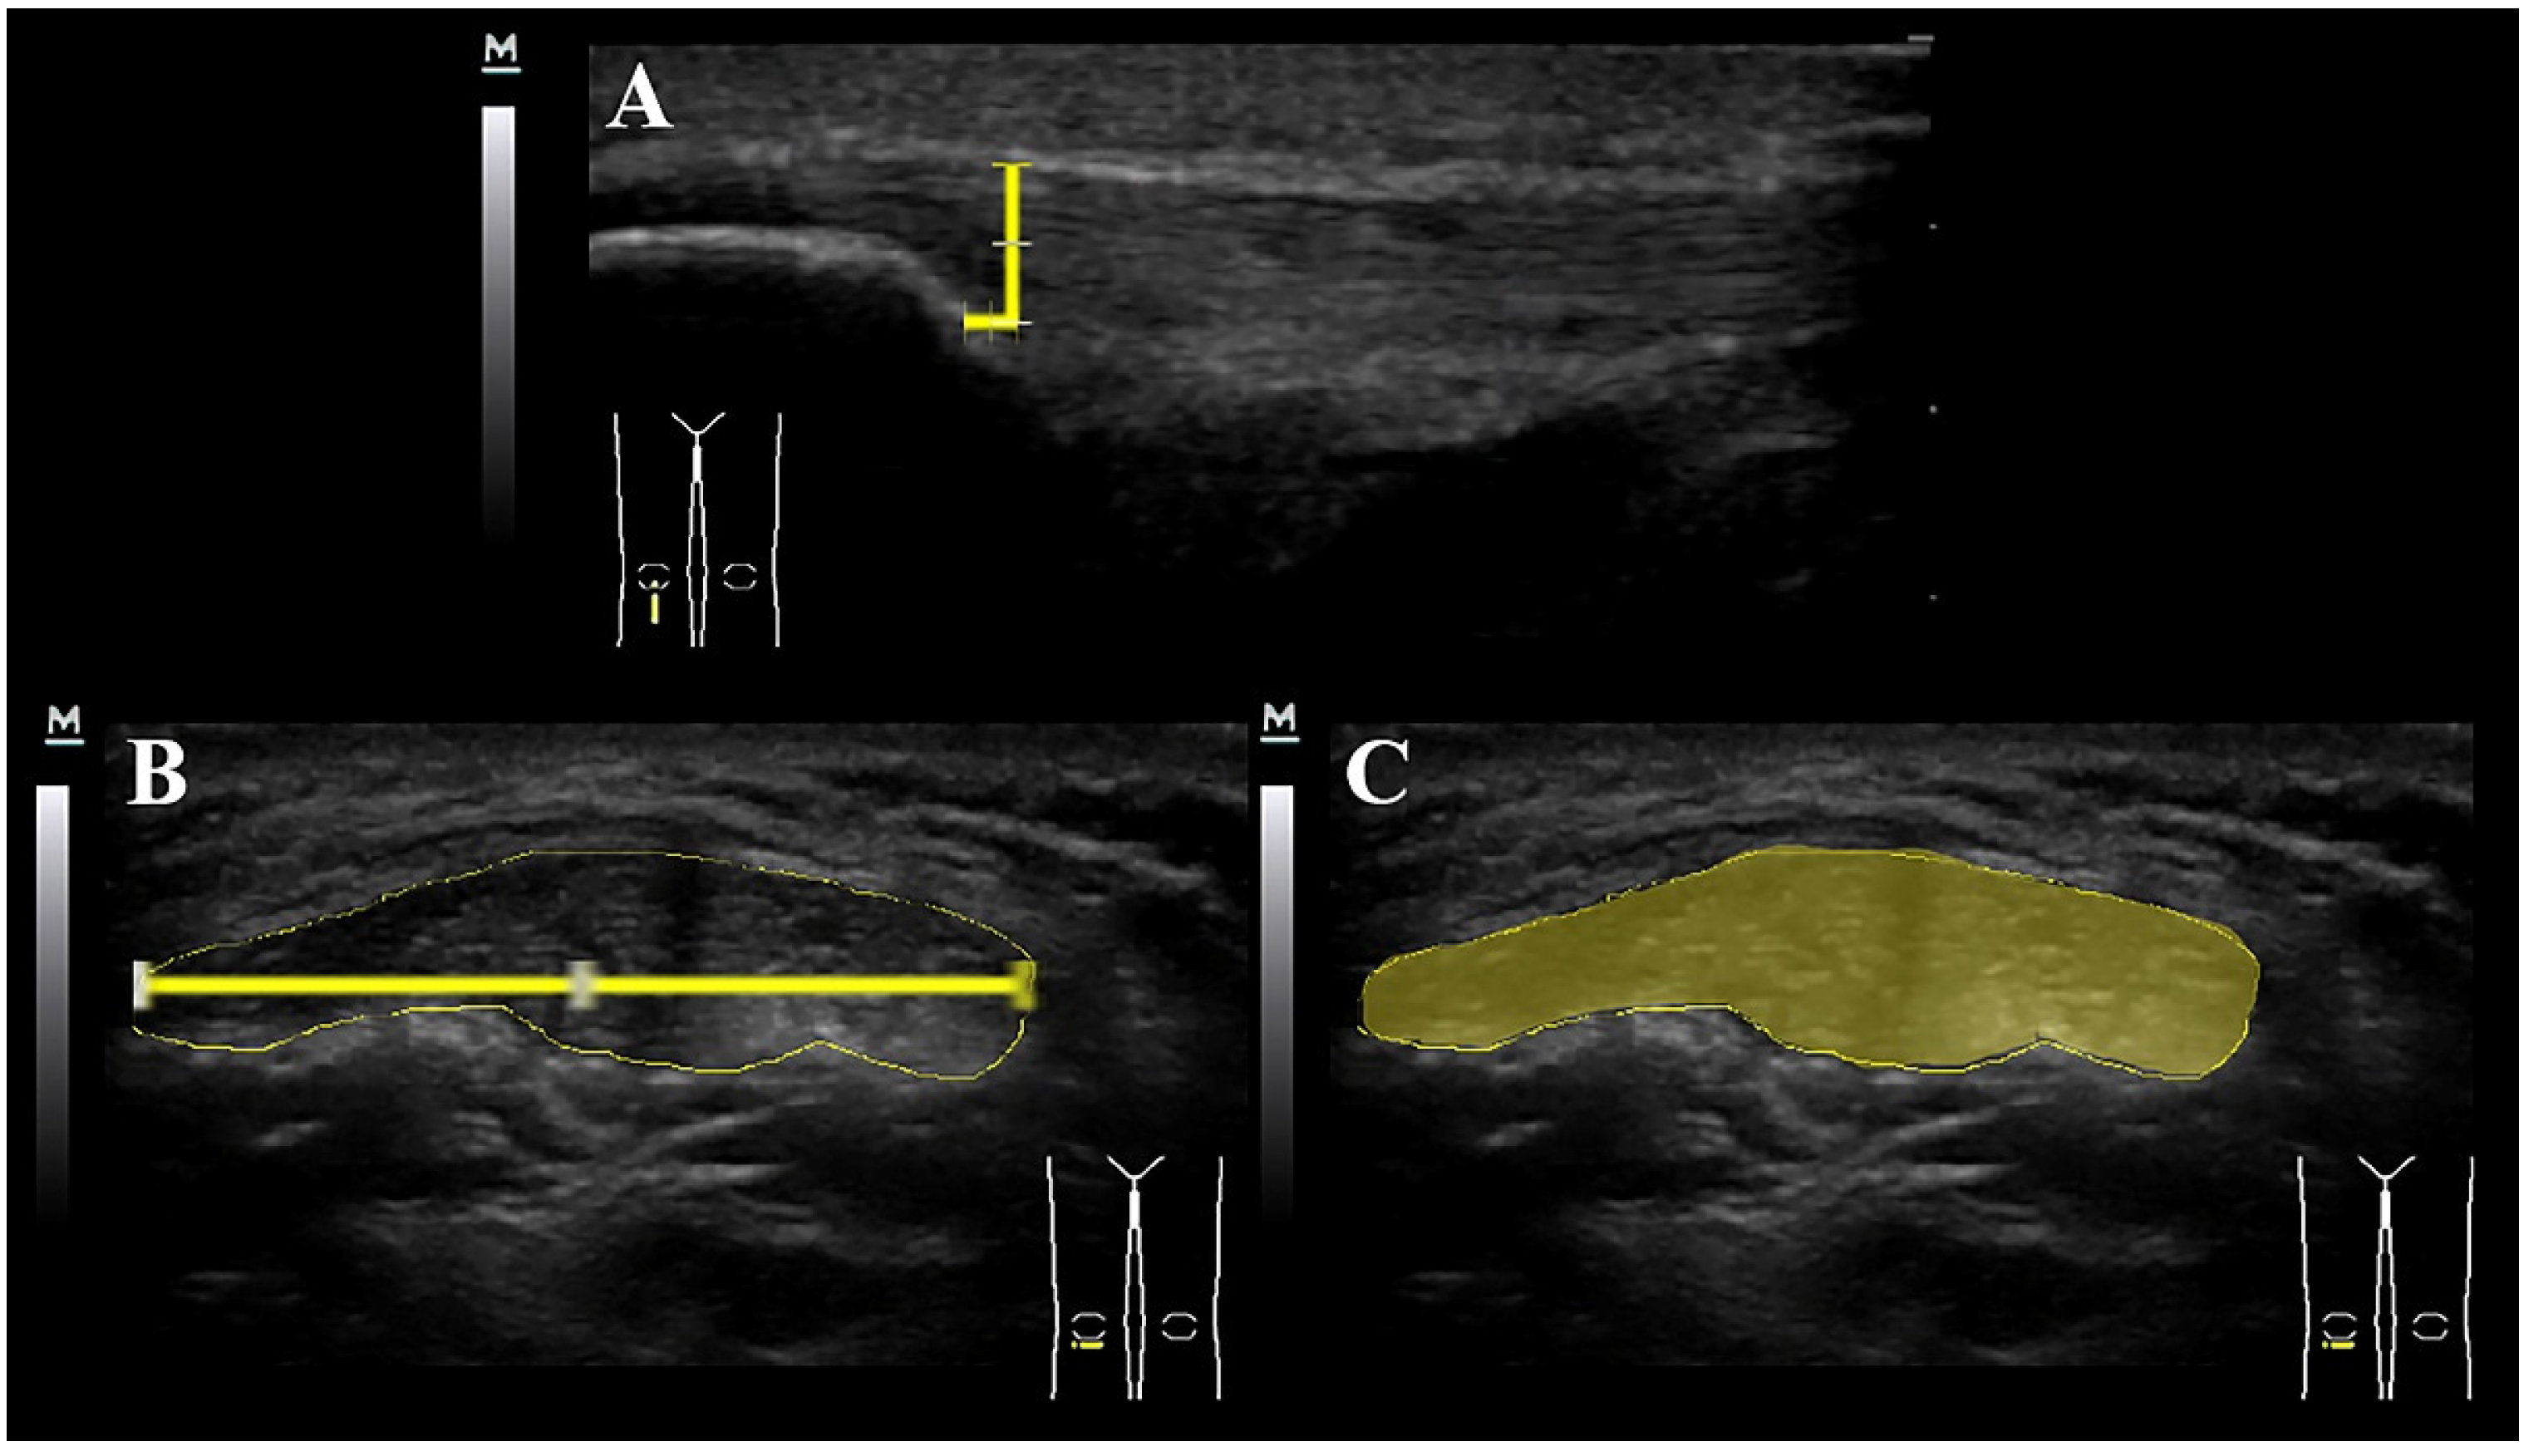

2.3. Ultrasound Imaging of the Patellar Tendon

- Martinoli, C. Musculoskeletal ultrasound: Technical guidelines. Insights Imaging 2010, 1, 99–141. [Google Scholar] [CrossRef] [PubMed]

- Skou, S.T.; Aalkjaer, J.M. Ultrasonographic measurement of patellar tendon thickness—A study of intra- and interobserver reliability. Clin. Imaging 2013, 37, 934–937. [Google Scholar] [CrossRef] [PubMed]

- Black, J.; Cook, J.; Kiss, Z.S.; Smith, M. Intertester reliability of sonography in patellar tendinopathy. J. Ultrasound Med. 2004, 23, 671–675. [Google Scholar] [CrossRef] [PubMed]

- Toprak, U.; Usuner, E.; Uyanik, S.; Aktaş, G.; Kinikli, G.I.; Baltaci, G.; Karademir, M.A. Comparison of ultrasonographic patellar tendon evaluation methods in elite junior female volleyball players: Thickness versus cross-sectional area. Diagn. Interv. Radiol. 2012, 18, 200–207. [Google Scholar] [CrossRef]